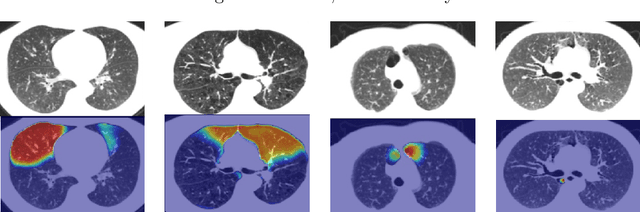

We propose a deep learning clustering method that exploits dense features from a segmentation network for emphysema subtyping from computed tomography (CT) scans. Using dense features enables high-resolution visualization of image regions corresponding to the cluster assignment via dense clustering activation maps (dCAMs). This approach provides model interpretability. We evaluated clustering results on 500 subjects from the COPDGenestudy, where radiologists manually annotated emphysema sub-types according to their visual CT assessment. We achieved a 43% unsupervised clustering accuracy, outperforming our baseline at 41% and yielding results comparable to supervised classification at 45%. The proposed method also offers a better cluster formation than the baseline, achieving0.54 in silhouette coefficient and 0.55 in David-Bouldin scores.